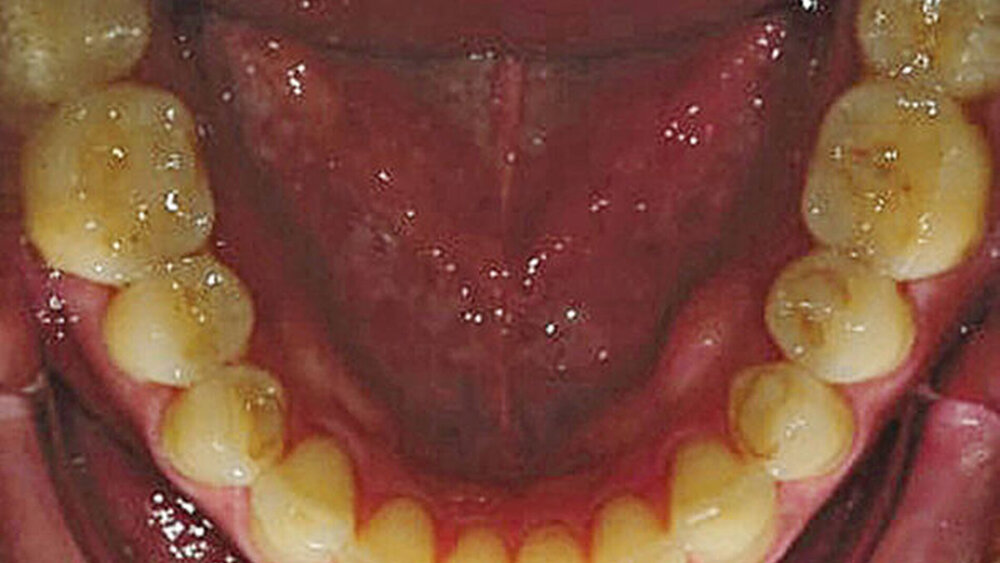

2015 stellte sich ein 47 Jahre alter Mann mit Schmerzen im TMG (Temporomandibulargelenk) vor. Er hatte außerdem ein ästhetisches Anliegen, da ein Stück vom Veneer eines mittleren oberen Schneidezahns abgebrochen war (Abb. 1–3). Die klinische und radiografische Analyse (Abb. 4) ergab einen Verlust der Bisshöhe und der Zahnsubstanz aufgrund von Bruxismus.

Digitale intraorale Fotos wurden aus der Vorderansicht unter Retraktion sowie aus der Okklusions- und lateralen Ansicht erstellt. Zudem wurden mit einer digitalen Spiegelreflexkamera (DSLR) zusätzliche Fotos erstellt (frontal, lateral und 45º). Eine diagnostische Abformung beider Kiefer wurde mit einem intraoralen Scanner (Carestream 3500) durchgeführt. Die maximale Interkuspidationsposition (MIP) wurde intraoral mit dem intraoralen Scanner Carestream 3500 erfasst, und die neue Vertikaldimension der Okklusion (VDO) wurde durch entsprechend weites Öffnen des virtuellen Artikulators in der CAD/CAM-Software (CAD/CAM = computergestützte Konstruktion und Fertigung) erreicht.